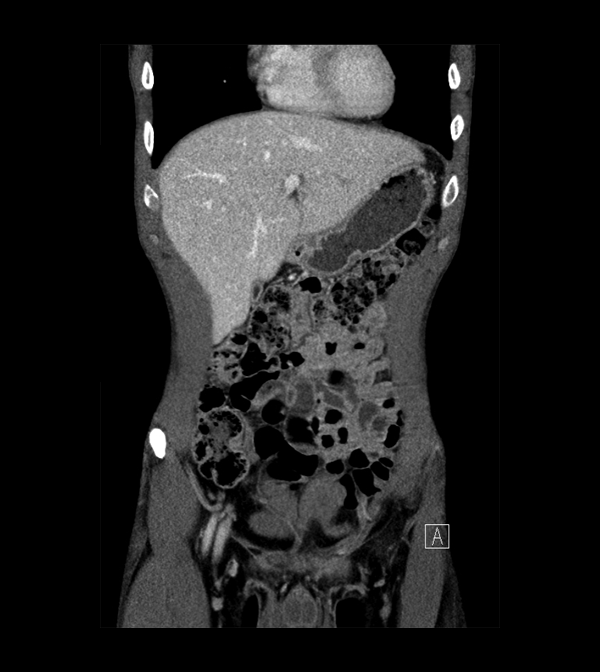

Body

Covers abdominal CT anatomy.